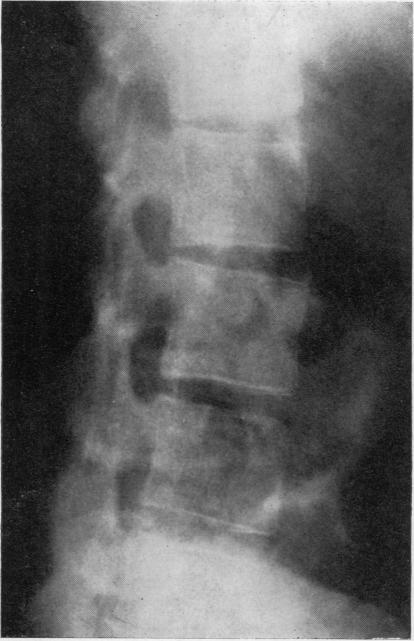

Radiological changes in the sacro-iliac joints and spine of patients with psoriatic arthritis and psoriasis.

Ann Rheum Dis. 1968 Jan;27(1):1-6. doi: 10.1136/ard.27.1.1.